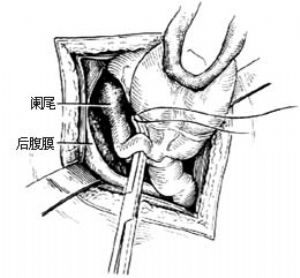

3.當闌尾位於盲腸後,位置固定不易切除時,可切開盲腸外下方的後腹膜[圖3 ⑴],再用紗布包住盲腸向上翻轉,露出闌尾後,作逆行闌尾切除術。另若闌尾較長伴管端粘連固定,不宜按常規勉強提出末端,改爲逆行切除闌尾。先用變止血鉗在靠近闌尾根部處穿過其系膜,帶過兩根4-0號絲線,雙重結紮闌尾根部[圖3 ⑵]。在結紮遠端1cm處夾一把彎止血鉗,用刀在止血鉗與結紮線之間切斷。闌尾殘端消毒處理後,根據具體情況行荷包縫合包埋或褥式縫合包埋。再用彎止血鉗向闌尾尖端方向分段鉗夾、切斷闌尾系膜[圖3 ⑶]最後切除闌尾,一一結紮近端闌尾系膜。